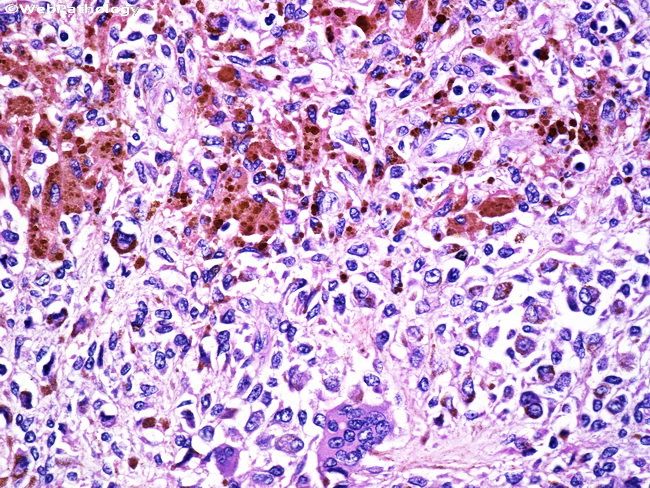

Пигментный виллонодулярный

Пигментный виллонодулярный 113 фотографий